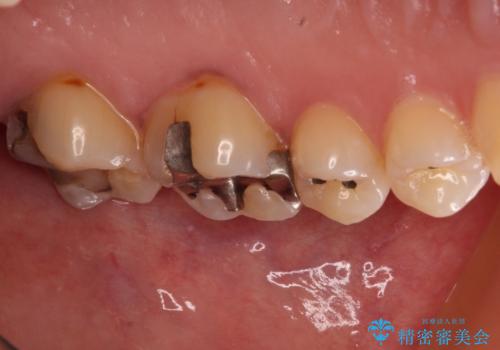

- 奥歯の銀歯がすぐに外れてしまうとのことで来院された患者様です。

何度か銀歯の詰め物を作ったものの、しばらくすると外れてしまうそうで、来院時には銀歯のない状態でした。

咬み合わせをみると、奥歯に負担がかかりやすいことが分かったので、適合がよく、硬さが歯と近いPGAインレー(白金加金合金インレー)にて修復治療を行うこととしました。